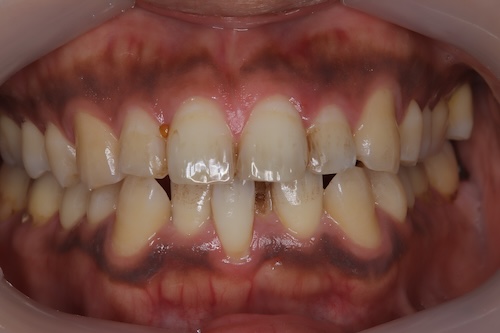

ホワイトニング症例報告

東京 ホワイトニングサロンボーテ神田の症例報告お客様情報

30代男性

初診時シェード: 右上1 C3、右下3 A4

目標シェード: BL4

ご家族から勧められてご来店くださいました。

叢生のため着色がつきやすい。ベリーホワイトで毎日磨いていただきました。